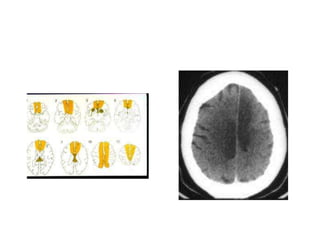

Posterior cerebral artery

• The posterior cerebral artery (PCA) arises from

the top of the basilar artery and feeds the

medial occipital lobe and inferior and medial

temporal lobes. Vision is the primary function

of the occipital lobe, so a stroke affecting PCA

distribution commonly causes visual deficits—

specifically contralateral homonymous

hemianopia.

Posterior cerebral artery •The posterior cerebral artery (PCA) arises from the top of the basilar artery and feeds the medial occipital lobe and inferior and medial temporal lobes. Vision is the primary function of the occipital lobe, so a stroke affecting PCA distribution commonly causes visual deficits— specifically contralateral homonymous hemianopia.